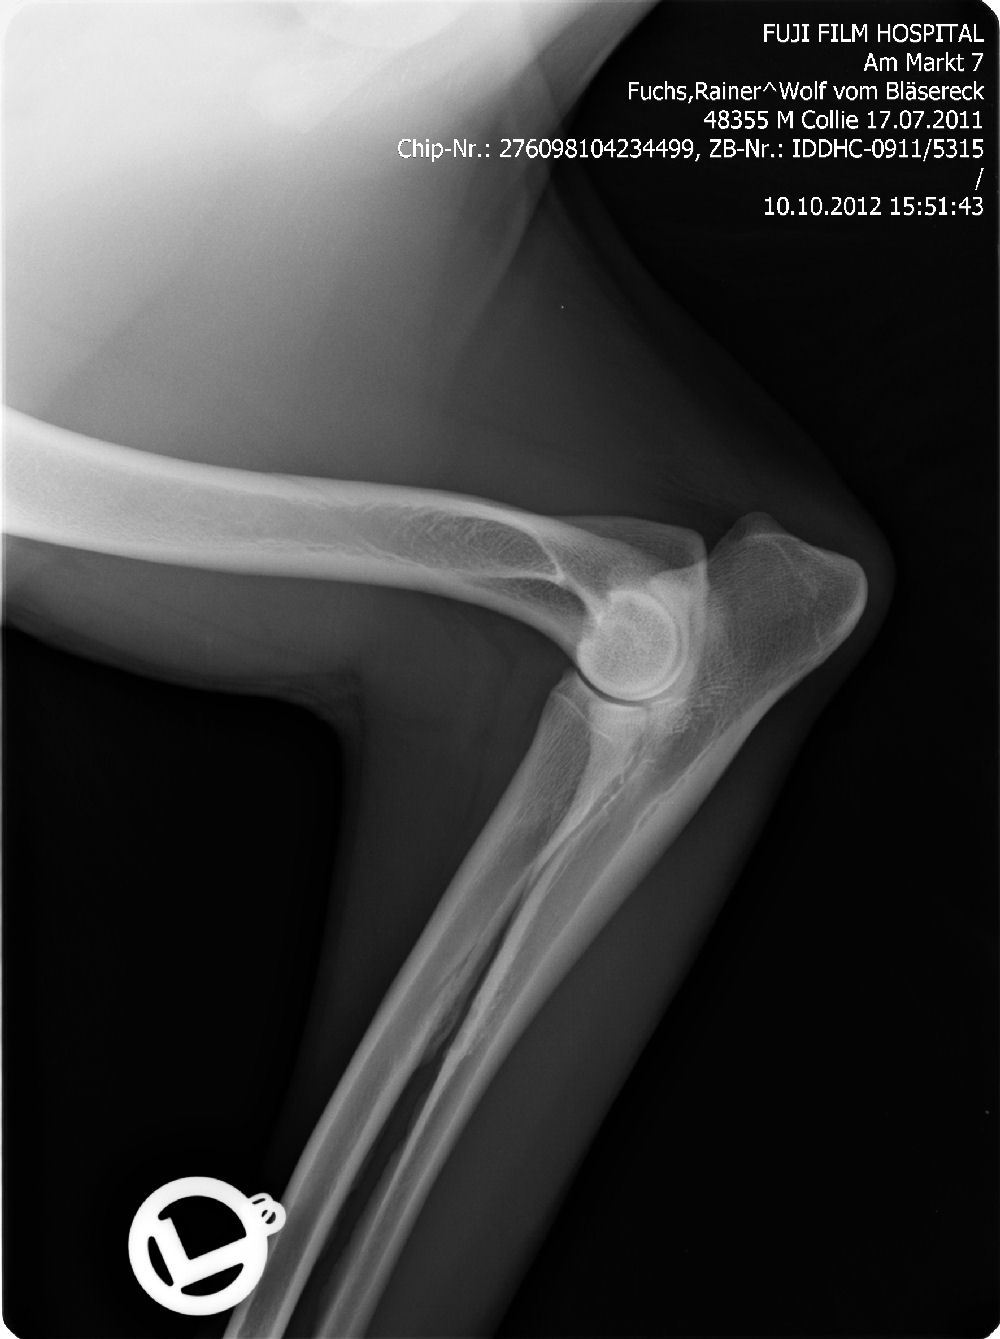

Ab dem Jahr 2008 wird nur noch Digitales Röntgen durchgeführt, da wir auch hier wieder führend und transparent sind, zeigen wir gern die Röntgenbilder ! Bei Züchtern, die dies nicht tun, haben Sie weniger Sicherheit !